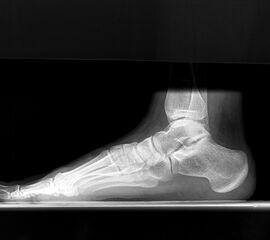

• Röntgenaufnahme des Fußes (unter Belastung) in dorsoplantarem und seitlichen Strahlengang (Abb. 2a-b).

• Beurteilung des proximalen Gelenkflächenwinkels der Grundphalanx (Proximal Phalangeal Articular Angle, PPAA) sowie des distalen Gelenkflächenwinkels der Grundphalanx (Distal Phalangeal Articular Angle, DPAA) 56 (Abb. 3c und 3d).

• Bestimmung des ersten Intermetatarsalwinkels (IMA, Abb. 3a), des Hallux valgus Winkels (HVA, Abb. 3a), des distalen metatarsalen Gelenskflächenwinkels (Distal Metatarsal Articular Angle, DMAA, Abb. 3b) 7. Möglicherweise muss die Akin-Osteotomie mit weiteren Eingriffen kombiniert werden (z.B.: retrokapitale Osteotomie oder andere metatarsale Osteotomie; Arthrodese).